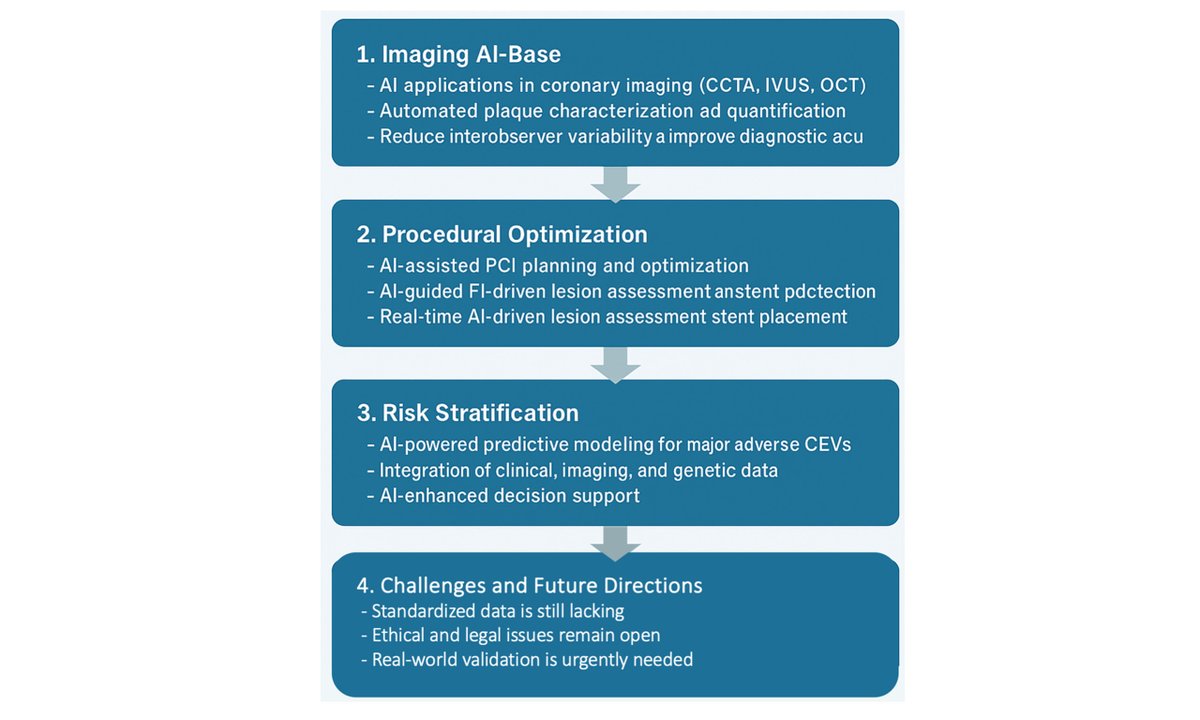

AI boosts precision in interventional cardiology but requires real-world validation. #ImagingAI #ClinicalAI #CardioInnovation @adrianocaixeta @drandrewsharp @rickytiago @DrSheilaSahni @TheNarulaSeries @MichaelMegalyMD @Pushpendraamu @JeremyKingPCI @alma_palau @kevinjamescroce

✨ AI in Interventional Cardiology 🤖 Improves imaging & plaque detection ⚙️ Aids planning, risk stratification 🌐 Needs validation & ethics #InterventionalCardiology #AI #PlaqueImaging 🔗 oaepublish.com/articles/2574-…